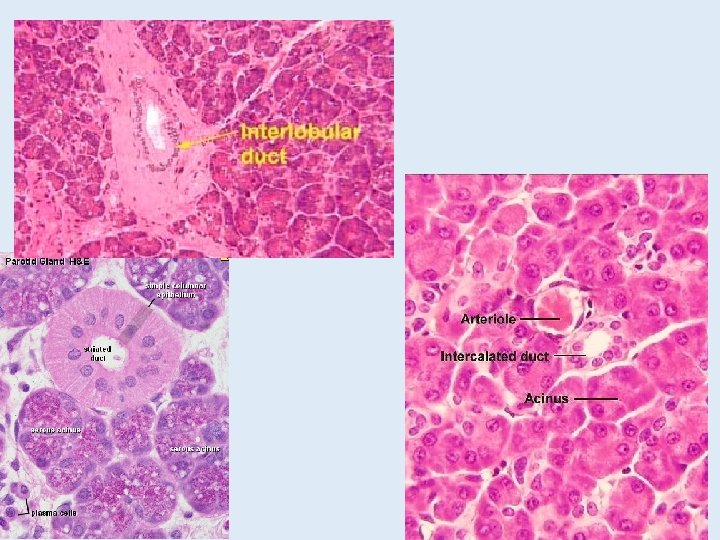

Salivary glands • Submandibular gland • Mixed gland Intercalated duct Striated duct Interlobular duct